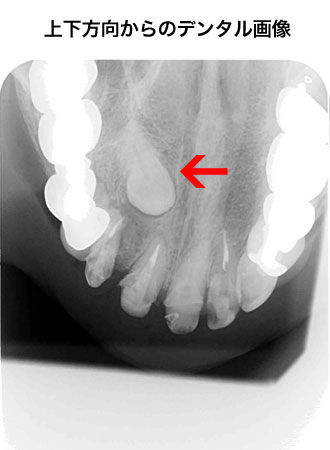

デジタルレントゲン

当院ではあえてCTを採用せず、デジタルパノラマ・セファロレントゲンを採用しました。

CTの1回あたりの撮影の際の被爆量は250μSであるのに対し、デジタルパノラマ・セファロレントゲンは10分の1の25μSvであるからです。

(デジタルパノラマ・デンタルレントゲンは10μS)

被爆量の低減について、医療側の努力が必要であるからです。

(例えば東京ニューヨーク間の往復の際の高度による宇宙船の増加は200μSであり、航空会社のフライトアテンダント・コックピットクルーは搭乗のローテーション、業務終了後のシャワーなどの対策をとっているといいます。)

3次元的なレントゲンの検査方法として、下記の様な物があります。

方向の異なる画像を読影して診断する事が可能です。